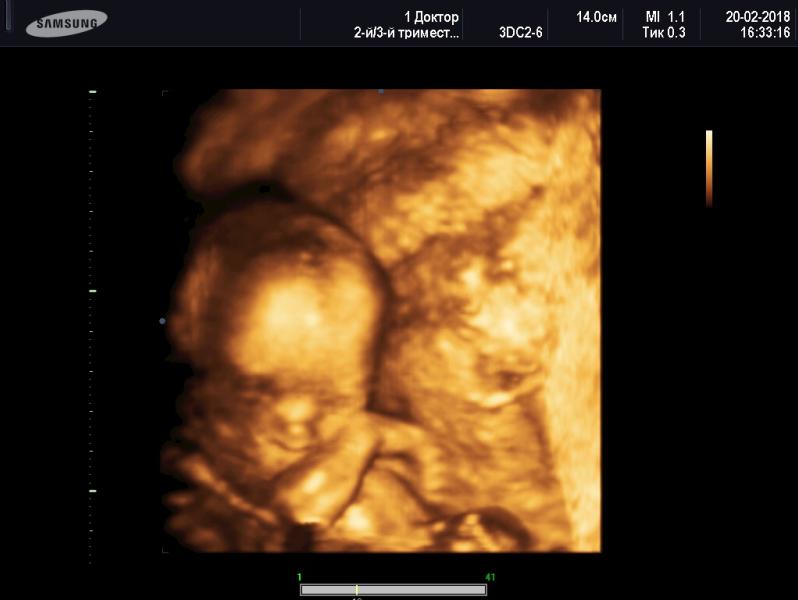

Сходили на 3Д УЗИ с мужем) и усе таки девочка Сашенька 100%. Девочки вы когда на УЗИ 3д ходили у вас у всех активно дети себя вели? Моя стояла на коленях то молилась, перевернулась начала ногами махать, руками и т д)

@romanova_alya, думала не выкладывать... как то это личное) при этом поняла вдруг кто захочет тоже на 3д посмотреть вот такую СВОЮ радость))😊